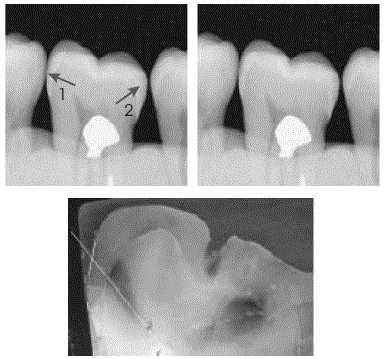

As imagens radiográficas ilustradas acima são relativas a uma mesma situação clínica e seu correspondente histológico. Considerando essas imagens, julgue os itens a seguir.

I A imagem radiográfica da superfície distal do molar apresenta

lesão cariosa de esmalte

.

II A imagem radiográfica da superfície mesial do molar

apresenta lesão em esmalte e dentina

III A lesão em dentina, presente na situação clínica acima, corresponde a lesão cavitada.

IV Há tratamento não-operatório adequado para a situação clínica acima.